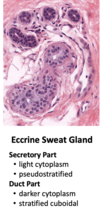

Eccrine sweat gland